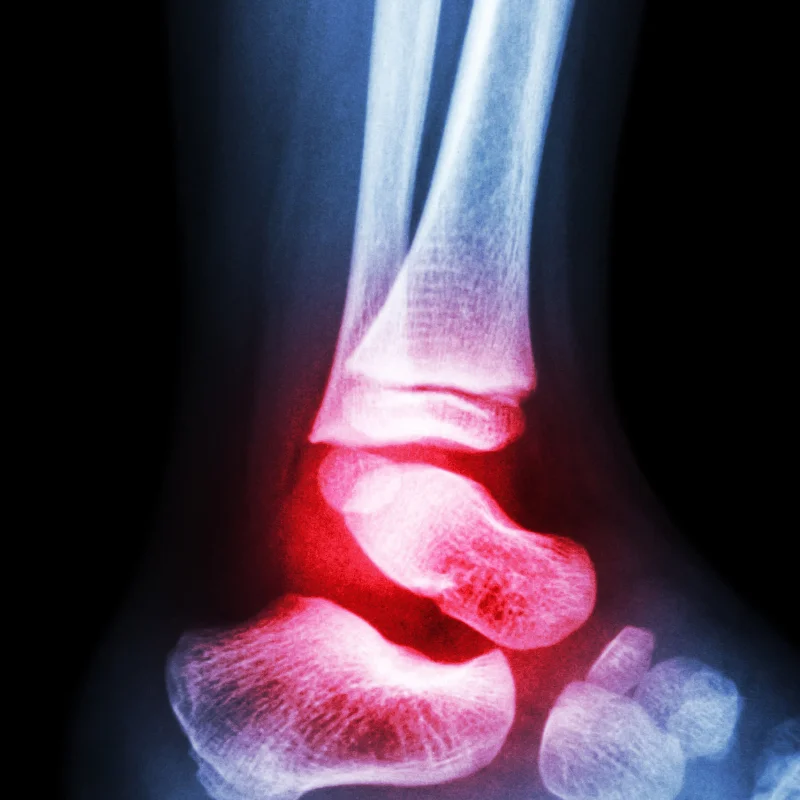

Rheumatoid arthritis is an autoimmune inflammatory disease in which synovial inflammation can drive pain, swelling, stiffness, structural damage, and systemic complications. Earlier researchers focused on the role of immune complexes, autoantibodies, and other circulating inflammatory mediators. That made plasmapheresis appealing in theory because the procedure can physically remove a portion of plasma and the substances carried in it (Seror et al., Transfusion and Apheresis Science, 2007).